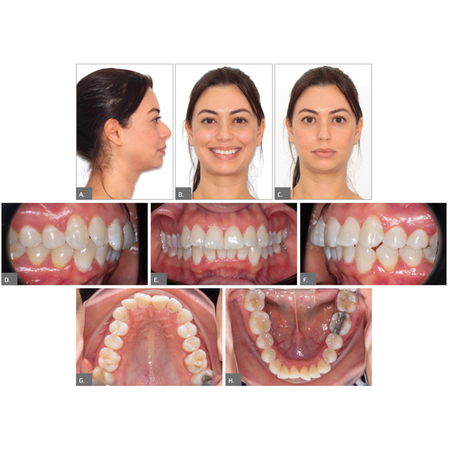

Compensación dentoesquelética extrema para mordida abierta anterior esquelética severa tratada con Invisalign

INTRODUCCIÓN: : La mordida abierta anterior es una maloclusión compleja, a menudo asociada con discrepancias esqueléticas y verticales. Con la evolución de la tecnología de alineadores transparentes, (los alineadores) Invisalign® se han convertido en una opción viable para el tratamiento de casos complejos con una planificación adecuada. CASO CLÍNICO: Este caso clínico describe el tratamiento de una paciente de 28 años con mordida abierta anterior esquelética severa y una...

Extreme dentoalveolar compensation of a severe skeletal anterior open bite with Invisalign®

INTRODUCTION: Anterior open bite is a challenging malocclusion, often associated with skeletal and vertical discrepancies. With the evolution of clear aligner technology, Invisalign® has become a viable option for treating complex cases when appropriately planned. CASE REPORT: This case report describes the treatment of a 28-year-old female patient with a severe skeletal anterior open bite and a slight Class III molar and canine relationship. The treatment involved the use of Invisalign®...